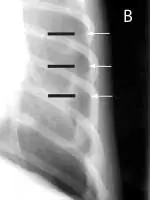

A radiograph shows the thoracic cavity of a dog, highlighting the heart and surrounding structures. The image reveals a potential abnormality in the heart's silhouette, with clear visibility of the ribs and spine in the background.

FIGURE 1

Pneumothorax is evident in this thoracic radiograph of a cat (A), as the cardiac silhouette is elevated from the sternum on the lateral projection and the lung lobes are collapsed. Close-up of the lateral view (B) shows air between the sternum and cardiac silhouette. In my experience, the lateral view is more sensitive for detecting pneumothorax because the elevation of the heart from the sternum is easily appreciated. When viewed from dorsoventral (DV) or ventrodorsal (VD) positioning, the lack of blood vessels extending out to the periphery and increased lucency of the lung fields could be overlooked.